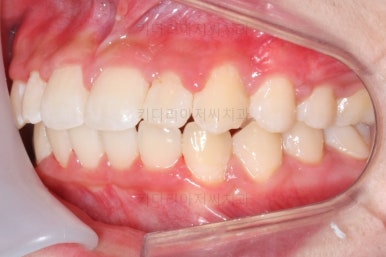

마무리 때의 모습입니다.

임시 개념으로 치아 사이즈를 키운건데 환자분은 만족하시나봐요.

보통 올세라믹, 라미네이트 등 보철치료는 성인이 되어서 해야해서 이래나 저래나 이정도에서 만족하기로 했습니다.

치아는 매우 가지런해졌고 뾰족하던 앞니의 형태도 좋아졌어요.

매복되어 있던 송곳니도 잘 나왔고 과개교합도 물론 개선이 되었습니다.

얼굴모습은 크게 바뀌진 않았어요.

대신 웃거나 말하는 모습에서 드러나는 치열은 매우 예뻐졌어요.